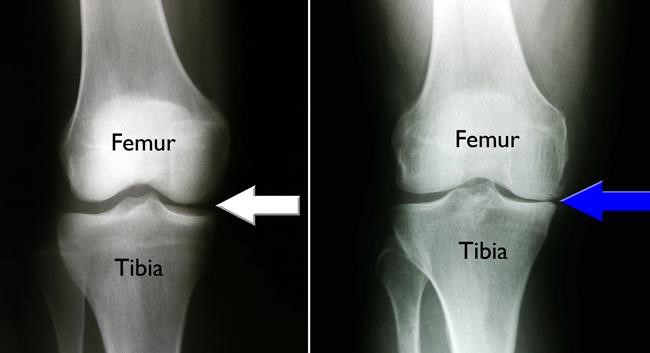

(Left) This x-ray of a healthy knee shows the normal joint space between the tibia and femur. (Right) In this x-ray, osteoarthritis has caused isolated damage to the inside portion of the knee. The tibia and femur are rubbing against each other, causing pain (blue arrow).